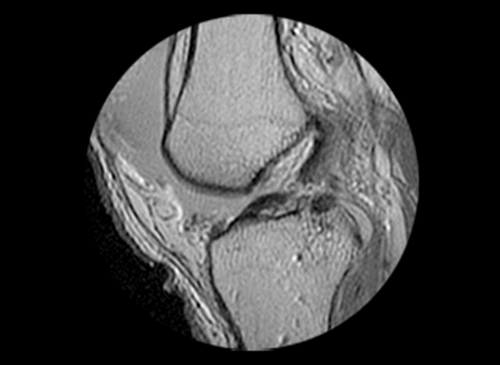

인대 재건술은 관절의 인대가 손상되었거나 파열되었을 경우 시행하는 수술법입니다.

전방, 후방 십자인대, 내-외측 측부인대 등 무릎 관절이 외부 충격이나 손상으로 제 기능을 상실할 경우 시행하는데 새로운 인대를 이식하여 원래의 기능을 되찾아주는 수술 방법입니다. 인대 재건술은 인대 파열 이후 생기는 인대 강도의 약화나 길이 변화에 대해 가장 확실하게 본래의 기능을 회복시켜주는 수술입니다.